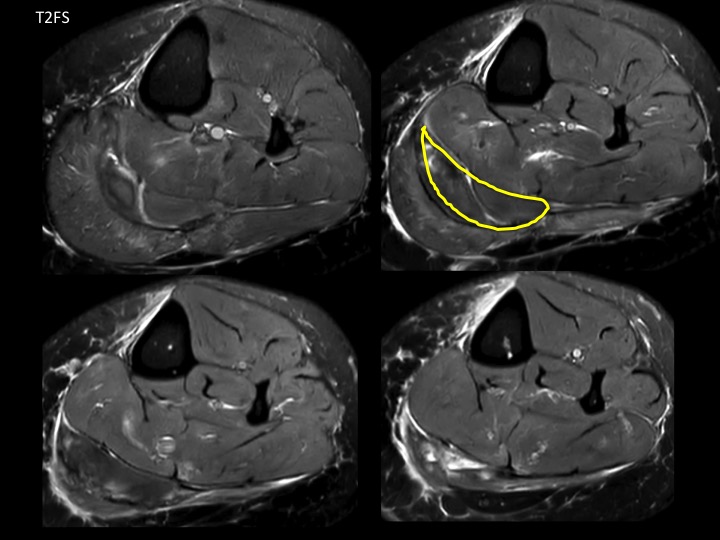

60F 3 weeks calf pain, suspect DVT

No DVT. Very subtle subacute full thickness tear at the distal myotendinous junction of the medial head gastrocnemius with 1.5 cm retraction at the tear and mild muscle edema. There is a subacute hematoma in the intermuscular fat planes (outlined in yellow) which is almost isointense to muscle, with a dark rim on ax T2FS and peripheral bright rim on T1. Easy to miss. Reference article.

medial head of gastrocnemius muscle ( RID2921 )